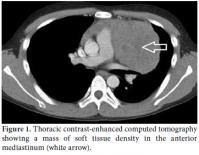

The patient was admitted to the rheumatology department at our West China Hospital in June of 2012 due to a two-month history of left chest pain accompanied by fatigue, accidental palpitation, and dyspnea. His lupus status was inactive at that time with a Systemic Lupus Erythematosus Disease Activity Index 2000 (SLEDAI-2K) score of 4 due to pleurisy and pericarditis. After thoracic computed tomography (CT), the existence of a tumor measuring 7.5x11.5 cm was confirmed in the anterior mediastinum (Figure 1). A percutaneous biopsy also suggested a type C thymoma (undifferentiated carcinoma) (Figure 2).[8] As a preoperative therapy, the patient had undergone four rounds of chemotherapy and 11 rounds of radiotherapy. At the one-year followup, his SLE was stable with a SLEDAI-2K score of 0.